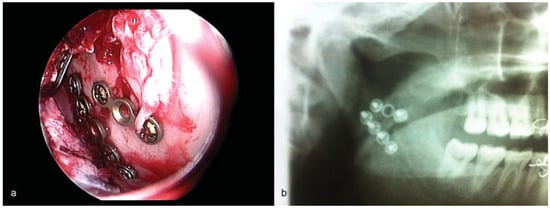

Figure 6.

(a) Two-year postoperative OPG showing restoration of posterior ramal height and healed fracture. (b) PA mandible shows restoration of mediolateral position of proximal segment.